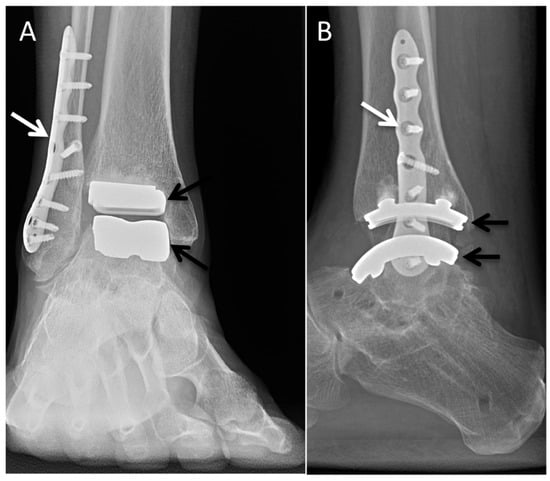

5.4. Total Ankle Arthroplasty

Funding